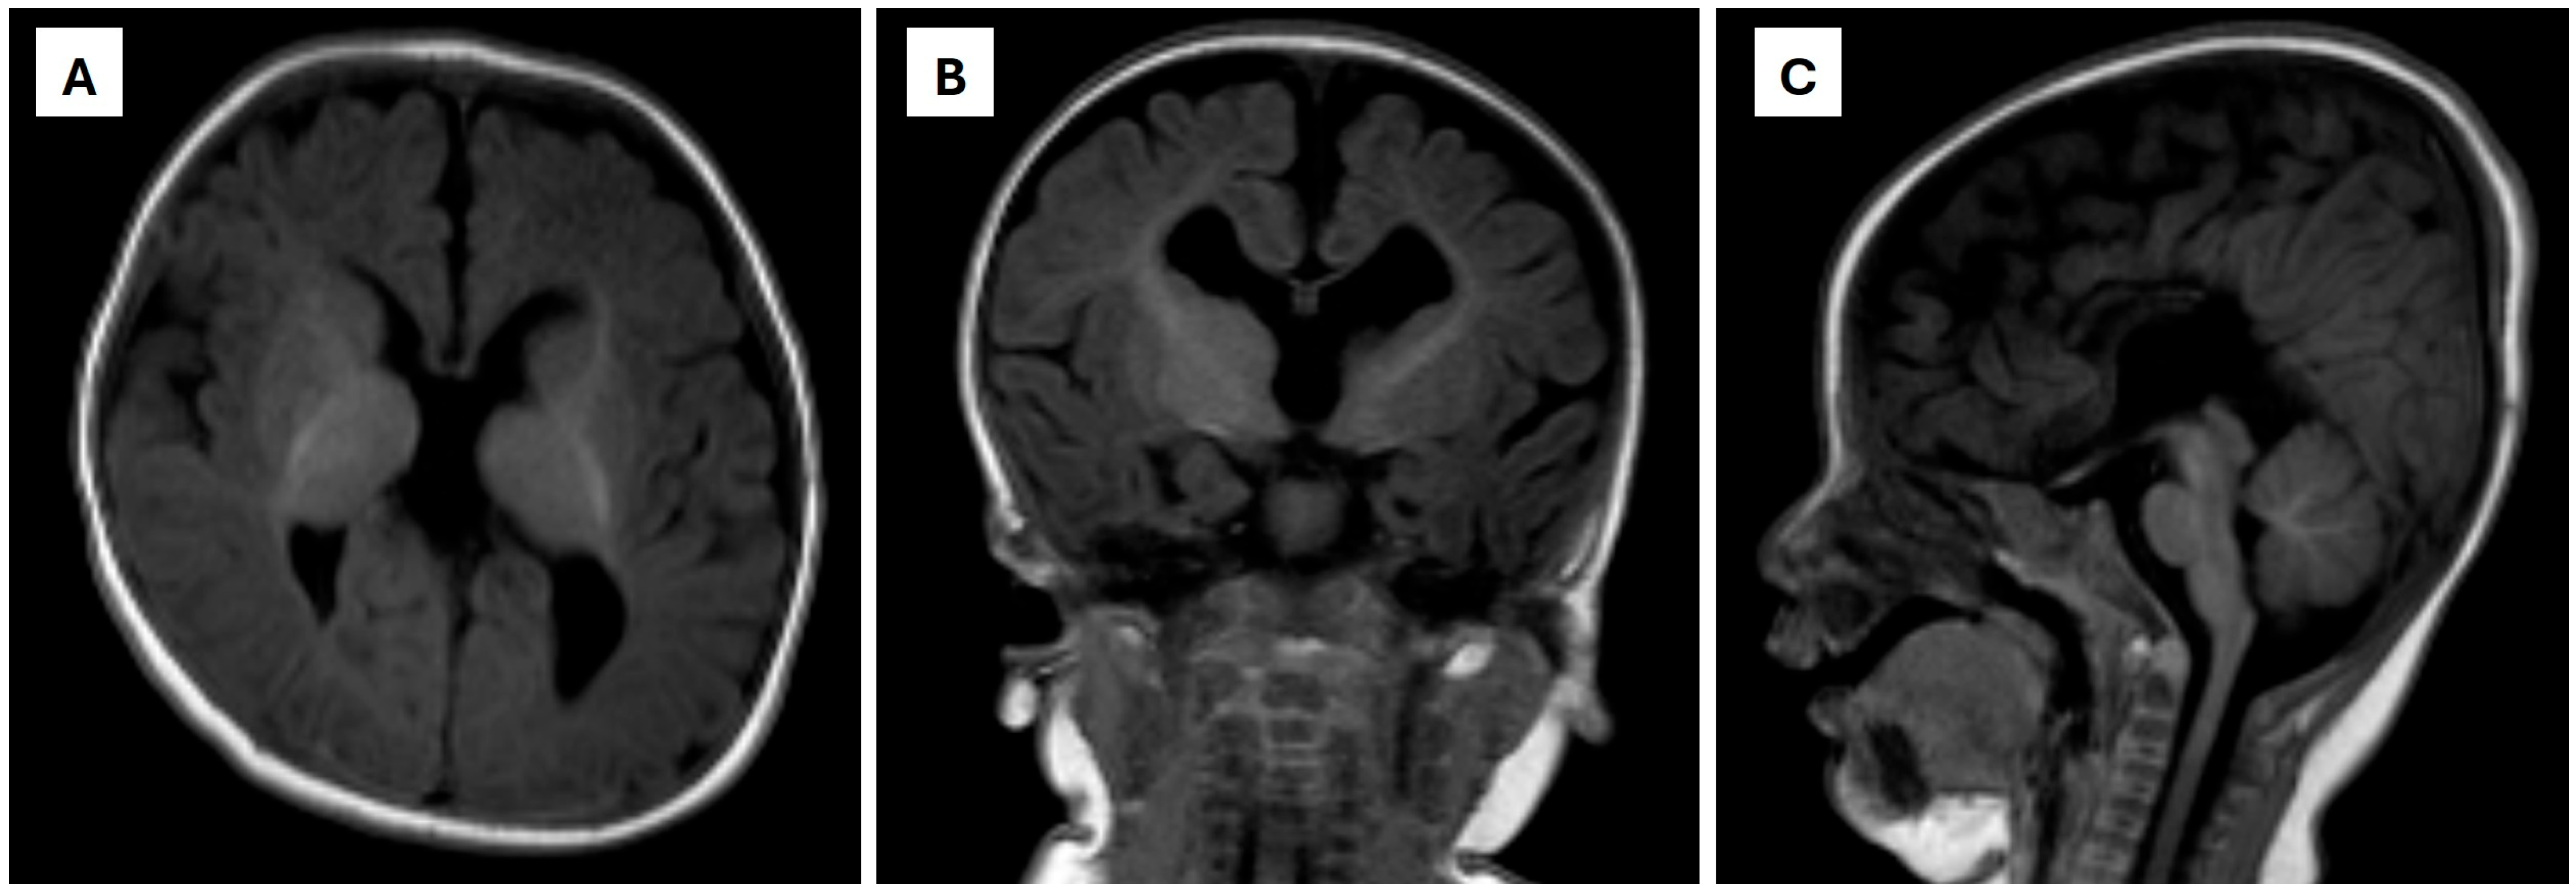

2. Case Presentation

| MRI | magnetic resonance imaging |